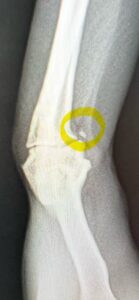

これーーーーーー!!!!

なぜかここにあるこれ。

骨が欠けたみたいです。(´;ω;`)ウゥゥ

これは痛いわ!

だってないものがここにあるんだもの・・・・

これだけ離れちゃっているけどもしかして癒着してくれる可能性もあるから

炎症止めの薬を5日間飲んで

経過観察で1か月。

癒着してくれるといいけども・・・・

もし、癒着しない場合、手術で欠けた骨、取るようなのかなぁ・・・

大豆ももう11歳だから手術はなるべく避けてあげたいんだけども・・・・